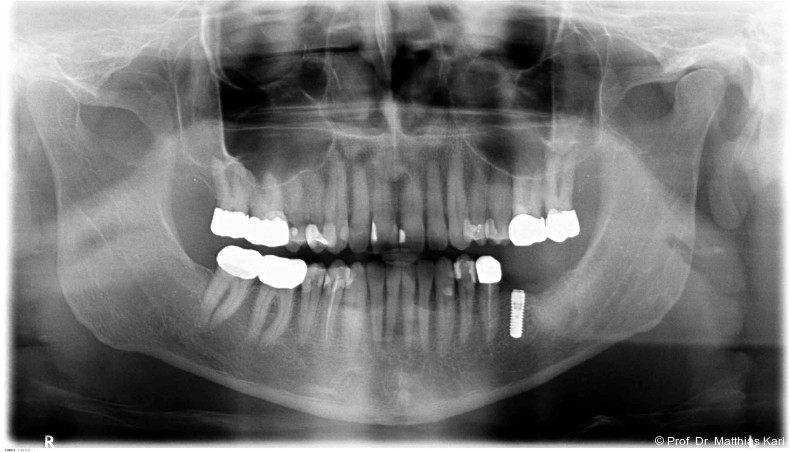

Mikrobewegungen im Verhältnis zum umgebenden Knochenlager. Die Vermeidung solcher Bewegungen ist essenziell, um eine erfolgreiche Osseointegration und damit die Entwicklung einer sekundären, biologisch bedingten Stabilität zu ermöglichen.18 Zur Verkürzung der Behandlungsdauer und zur Ermöglichung einer frühzeitigen prothetischen Versorgung wurden die klassischen operativen Protokolle angepasst. Hierzu zählen die untermaßige Implantatbettpräparation7 sowie der Einsatz konischer Implantatkörper21 (Abb. 1a–2b) mit ausgeprägt aggressiver Gewindegeometrie.8, 14 Beide Maßnahmen führen zu einer erhöhten Kompression des Alveolarknochens, insbesondere in den kortikalen Anteilen.11, 22

Zur Reduktion der Knochenkompression, insbesondere der bukkal gelegenen Lamelle (Abb. 3), werden derzeit Implantate mit dreieckigem Querschnitt10, 12 sowie Implantate mit zervikal reduziertem Durchmesser16 angeboten. Diese scheinen jedoch im Gegensatz zur subkrestalen Positionierung (Abb. 4a–c) von Implantaten23 keine signifikanten Vorteile zu bieten. Bohrprotokolle, welche sowohl auf das jeweilige Implantatsystem als auch auf die vorliegende Knochenqualität abgestimmt sind, haben ebenfalls das Ziel, zu hohe Einbringdrehmomente zu vermeiden.